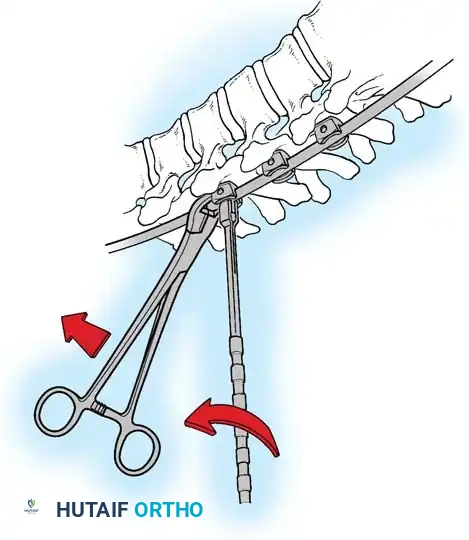

The Hall Technique

The Hall technique offers an alternative method for facet obliteration and grafting, particularly useful in rigid deformities.

Fig. 38-28: The Hall technique of facet fusion, involving sharp excision of the inferior facet and trough creation.

- Sharply amputate the inferior articular facet with a gouge and remove the bone fragment entirely. This exposes the cartilage of the superior facet.

- Remove the exposed cartilage completely with a sharp curet.

- Create a bleeding trough by removing the outer cortex of the superior facet.

- Impact cancellous bone grafts directly into this vascularized trough.

- Complete the procedure with global decortication of the posterior elements.